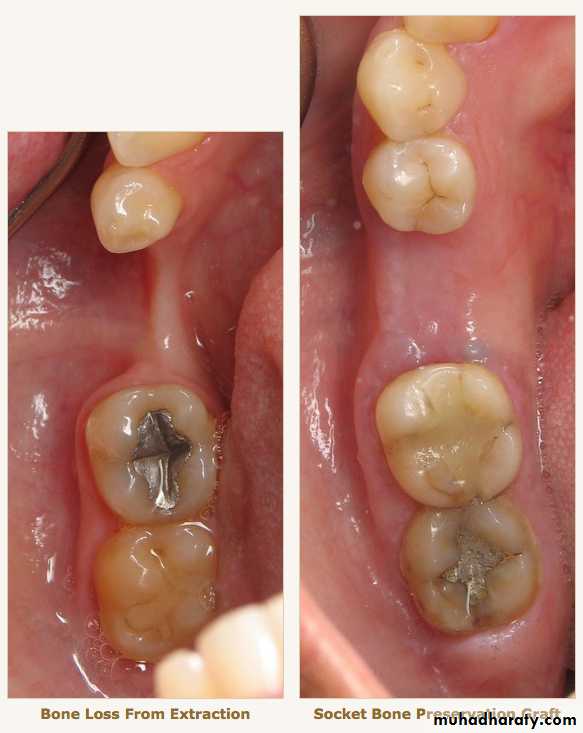

Radiographic examination:

• Cyst

• Tumor

• Retained root

• Periodontal condtion of remaining teeth

• Bone fracture

• Extend of bone resorbtion

• Locate cannal

• pt. education